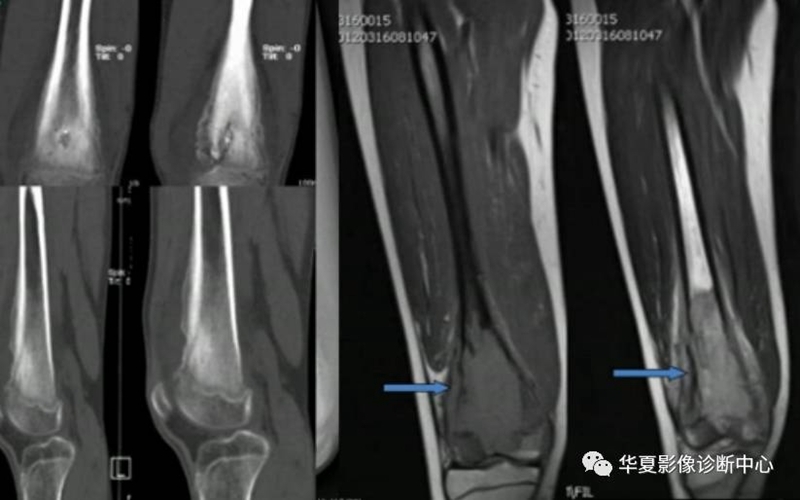

骨样骨瘤良性骨膜反应,骨肉瘤恶性骨膜反应